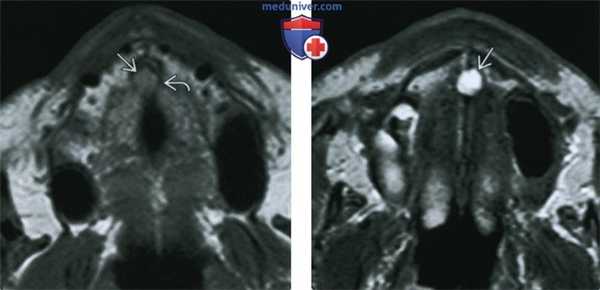

5. МРТ при кисте носонебного протока:

• Т1 ВИ:

о Однородный изо- или гиперинтенсивный сигнал

• Т2 ВИ:

о Однородный гиперинтенсивный Т2 сигнал

• Контрастное усиление обычно отсутствует:

о Воспалительный компонент может накапливать контраст

(Слева) На аксиальной МРТ (Т1 ВИ) определяется вздутие резцового канала с промежуточным - слегка гиперинтенсивным Т1 сигналом, обусловленное КННП. Обратите внимание на истонченную, но в остальном сохранную кортикальную пластинку.

(Справа) На аксиальной MPT (Т2 ВИ) определяется классическая КННП. Обратите внимание на срединное округлое включение с однородным гиперинтенсивным Т2 сигналом в верхней челюсти.

4. МРТ при кисте носонебного протока:

• Т1 ВИ: равномерно изо- или гиперинтенсивный сигнал, Т2 ВИ: гиперинтенсивный сигнал

• Обычно не накапливает контраст:

о Накопление контраста связано с воспалением

(Слева) При МРТ Т1ВИ в аксиальной проекции определяется расширение резцового канала со слегка гиперинтенсивным сигналом, обусловленное кистой носонебного протока. Обратите внимание на сохранный, но истонченный кортикальный слой.

(Справа) При МРТ Т2ВИ в аксиальной проекции визуализируется киста носонебного протока, имеющая «классический» вид. Киста выглядит как округлое гиперинтенсивное образование верхней челюсти, имеющее однородную структуру и располагающееся по средней линии.